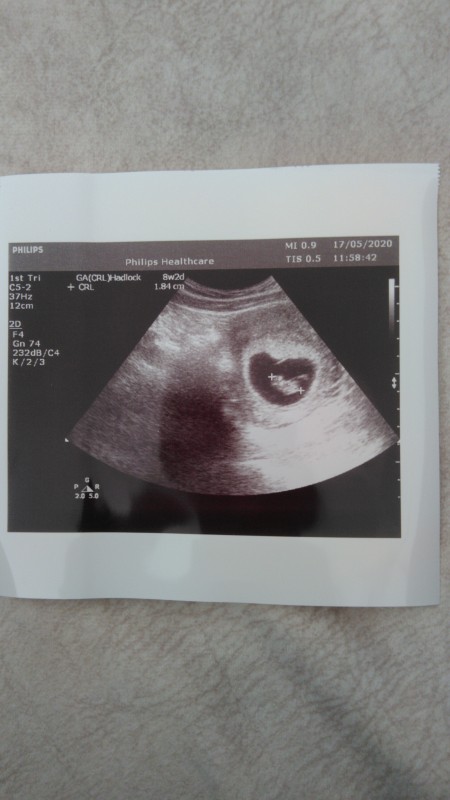

Bu şekilde mi acaba,

image

Bu benim bebiş de, kalbin içinde duruyo sanki

Yok cnm bu degil bence kesenin sekli bu. 3 d 4d cihazlarda gozukuyo hamileyken

(230 puan)

Bu bebegn kesesi:-)